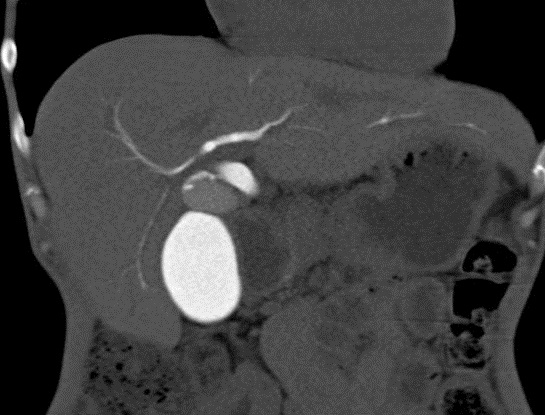

Image radiologique d'une CSP en

coupe TDM axiale avec de conrtrast

intraveineuse . Aspect de dilatation et

stricture stenosant systematise des voies

biliaires intrahepatique . Foie

elargir et splenomegalie |